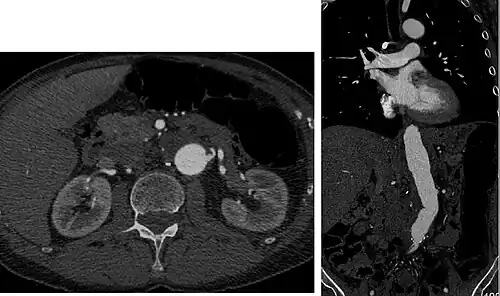

Axial and coronal view of abdominal CT angiography

CTA can be used in the chest and abdomen to identify aneurysms in the aorta or other major blood vessels. These areas of weakened blood vessel walls that bulge out can life-threatening if they rupture. CTA is the test of choice when assessing aneurysm before and after endovascular stenting due to the ability to detect calcium within the wall.[3] Another positive of CTA in abdominal aortic aneurysm assessment is that it allows for better estimation of blood vessel dilation and can better detect blood clots compared to standard angiography.[4]